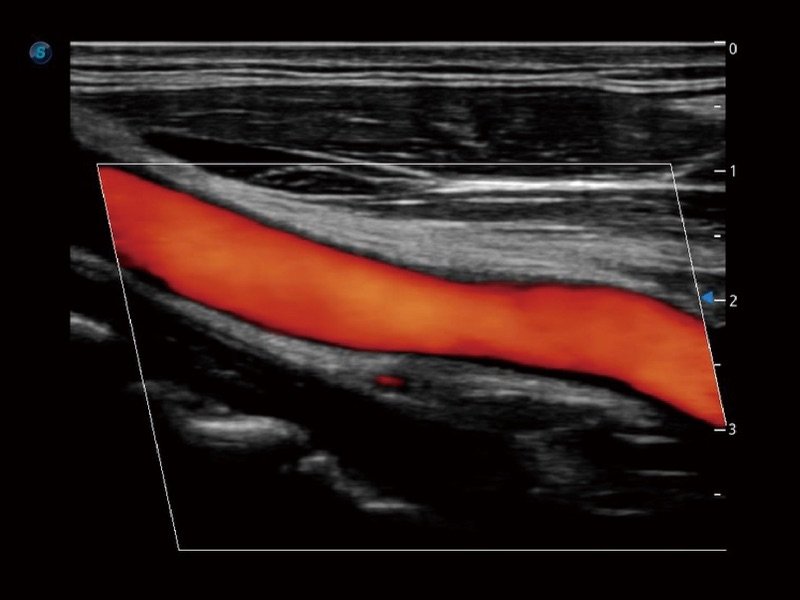

SR-Fluss

Als neue innovative Technologie verbessert SR Flow die Fähigkeit, Signale auch bei langsamer Strömungsgeschwindigkeit zu erkennen. Gleichzeitig wird die räumliche Auflösung verbessert und der Overflow überwunden, um dem Benutzer reale hämodynamische Daten zu liefern.